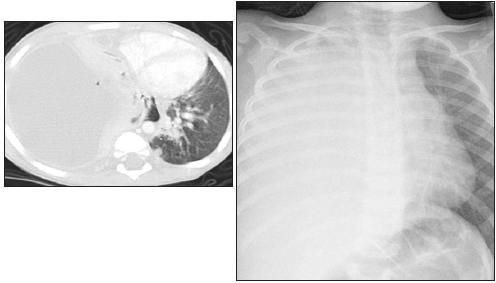

Over the past 10 years, CA-MRSA has become commonplace in many communities. CA-MRSA, which often carries the gene Panton-Valentine leukocidin, has been associated with pneumonia, particularly necrotizing pneumonia and empyema (Figure 2).14,42,43 Unlike nosocomial MRSA, CA-MRSA often remains susceptible to trimethoprim/sulfamethoxazole and clindamycin.44,45

Figure 2 – A 6-month-old girl was admitted with acute onset of fever and respiratory distress. A chest radiograph revealed almost complete opacification of the left hemithorax. A CT scan of the chest demonstrated consolidation of the left lung with low density within the lung, consistent with necrosis, and a large loculated pleural effusion. Drainage of the empyema was performed, and methicillin-resistant

Staphylococcus aureus

was identified as the pathogen.